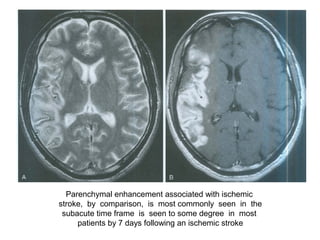

Post Gadolinium study

Parenchymal enhancement associated with ischemic

stroke, by comparison, is most commonly seen in the

subacute time frame is seen to some degree in most

patients by 7 days following an ischemic stroke